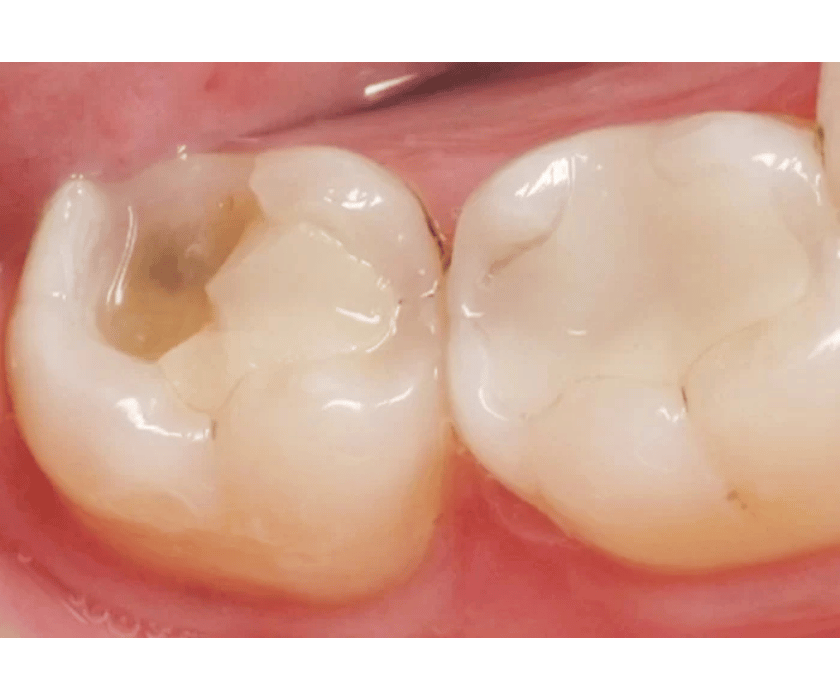

Sâu răng được điều trị bít trám bằng vật liệu composite

- Bước 3: Trám và tạo hình: Vật liệu Composite sẽ được đưa vào lỗ sâu hoặc vị trí răng bị mẻ. Bác sĩ sẽ tạo hình miếng trám để nó hòa hợp với hình dáng răng ban đầu.

- Bước 4: Chiếu đèn và đánh bóng: Dưới ánh sáng từ đèn chiếu chuyên dụng, miếng trám sẽ đông cứng ngay lập tức. Cuối cùng, bác sĩ sẽ đánh bóng miếng trám để tạo bề mặt mịn màng, tự nhiên và chống bám màu.

Vật liệu trám thẩm mỹ phổ biến nhất hiện nay là Composite. Composite là một loại nhựa tổng hợp, có thể được chế tác với nhiều màu sắc khác nhau để phù hợp với màu răng của mỗi người. Nhờ đó, miếng trám sẽ hòa hợp hoàn toàn với răng thật, khó có thể nhận ra bằng mắt thường.